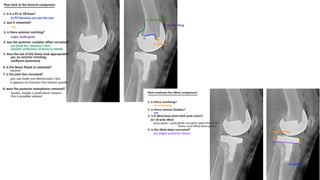

• STANDING XRAY OF KNEE AP AND LATERAL VIEW

SCANNOGRAMANDPATELLA